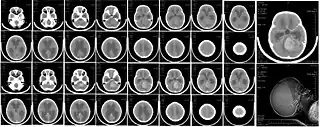

La mayoría se visualizan como una lesión sólida que realza con contraste al realizar la tomografía axial computarizada (TAC) o resonancia magnética (RMN) aunque el aspecto puede variar y verse algo difuso principalmente en niños menores de 3 años. La localización del tumor suele ser sobre la línea media del cuarto ventrículo (localizaciones laterales suelen ser más común en adultos). Es muy probable que se observe de hidrocefalia. Su principal diagnóstico diferencial al valorar las imágenes es el ependimoma.

- TAC: Hiperdenso (alta celularidad); Contraste: aún más hiperdenso. Calcificaciones en el 20% de los casos.

- RMN cerebral: T1WI: hipo a isointenso; T2WI: heterogéneo por tumor quístico, vasos y calcificaciones. Contraaste: marcada hiperintensidad.